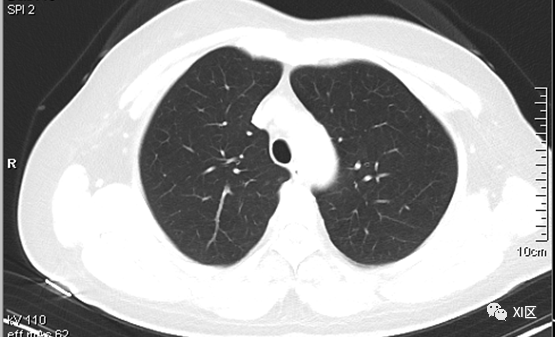

文章插图

图片源自网络 图文无关